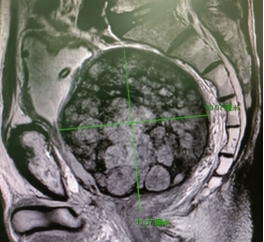

患者,石先生,78岁,8年前因排尿困难确诊为前列腺癌,前列腺体积巨大,当时考虑手术风险太大,选择了手术去势+氟他胺的治疗方案,并先后经历了阿比特龙、瑞维鲁胺+戈舍瑞林的内分泌治疗,及全身化疗等不规律的治疗,肿瘤指标PSA及排尿症状一直控制不佳。2年前因排尿明显困难接受了膀胱造瘘治疗,并出现大便也越来越困难,当地查PSA高达187ng/ml,MRI示前列腺巨大(640克),伴全身多处骨转移。根据石先生家人的回忆,老人家每次的排大便都慢长且痛苦,并开始因大便困难伴腹部胀满不敢进食。

巨大的前列腺肿瘤占据整个盆腔,明显挤压尿道及直肠

今年1月,经过当地医生推荐,石先生在子女的陪同下,找到我院泌尿外科邹志辉教授。住院后MRI检查显示患者前列腺癌体积超大(600 ml),并且对其尿道及直肠造成严重的阻梗,已危及患者的生命安全。针对石老先生的病情,在完善麻醉科、胃肠外科、介入科及心内科等多学科会诊后,由泌尿外科学科带头人梁朝朝教授,病区主任邰胜教授组织了科室疑难病例讨论,讨论一致认为手术解除梗阻已经刻不容缓,手术方案最终确定为“双侧髂内选择性动脉栓塞术+经尿道前列腺剜除术”,但手术难度及风险极大,充满变数,需作好手术失败及结肠造口的准备。